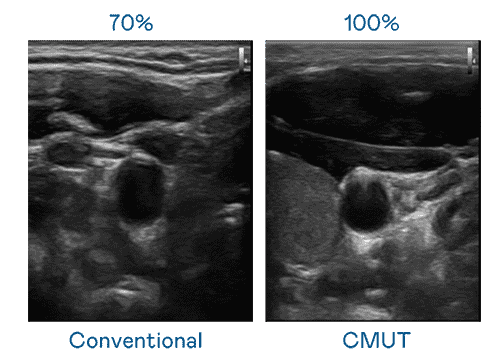

CMUT 技术是一种用电容式微机电元件来产生超音波讯号的技术。。。与传统 PZT 压电式技术相比,,CMUT 频宽增加 30%,,,,更宽频的超音波讯号让影像解析度大幅提升,,,,是实现高影像品质医疗超音波扫描、、、、促进精准医疗发展的关键技术。。。

大频宽带来超清晰影像

超音波影像的解析度高低,,首先取决于探头能发出的讯号频宽。。。糖果派对 CMUT 可提供高清晰的超音波讯号,,,提供高频宽、、高灵敏度、、影像纹理细节更高的超音波影像,,,协助医护人员缩短影像判读时间及利用精准的医疗影像进行诊断。。。